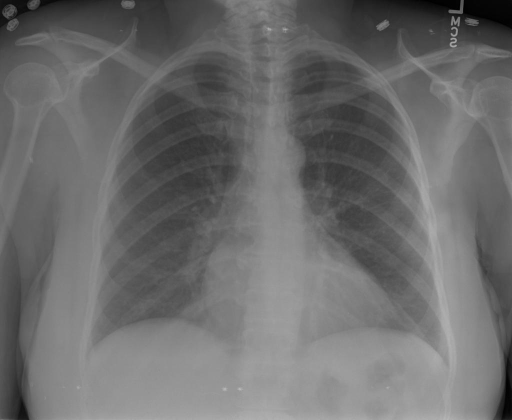

- (1)准备[诊疗报告(中文)](./data/Xray/openi-zh.json)和[X光影像](https://pan.baidu.com/s/13GBsDMKf6xBZBSHpoWH_EA?pwd=k9sh)在`data/Xray`文件夹下; - (2)开始训练: ```bash # 设置CUDA变量,主要是为了解决有时候直接训练而出现无法正确加载到显卡问题 export CUDA_VISIBLE_DEVICES=0,1,2,3 # 开始训练 bash finetune_XrayGLM.sh ``` 这里的复现过程非常简单,主要是很多过程我们都为大家准备好了,大家可以随时复现一个自己的`XrayGLM`。 ### 4.模型训练(通用) ## 效果展示 *以下效果来自于**低质量**的数据训练和权重 影像诊断: |X光影像|诊疗报告(医生)|XrayGLM| |:-|:-|:-| |![](./data/Xray/2_1.png)|根据X射线图像,心脏大小正常,肺部看起来很清晰。已经排除了肺炎、积液、水肿、气胸、腺病、结节或肿块的存在。该发现表明一切正常。换句话说,总体印象是胸部正常。|X光片显示,心脏大小正常。肺部没有气胸或胸腔积液的证据。骨骼结构看起来没有任何异常。总的来说,X光片表明没有发现急性心肺疾病的迹象。| |![](./data/Xray/2882_1.png)|X光图片显示没有扭曲的区域、可疑的骨质不透明度或胸腺积液。心脏大小轻微增大,但非常稳定。此外,没有气胸的证据,肺野也正常。总体来说,X光片显示没有急性心脏异常,但要注意轻微的心脏扩大。|X光片显示,心脏大小正常。肺部和纵隔轮廓清晰,没有气胸或胸腔积液的证据。骨骼结构完整,没有任何急性异常。| |![](./data/Xray/2577_1.png)|心影形态在正常范围内。没有急性骨质异常。有可能出现没有明显的吸水或肺实质状况的线索。没有大面积积液或气胸。有可能怀疑其有误吸或肺实质问题。为了确诊和治疗,可能需要进行适当的影像学随访。|心脏大小正常,肺部和纵隔轮廓清晰。没有急性异常或活动受限的证据。没有任何明显的气胸、胸腔积液或肺不张的迹象。此外,也没有发现任何局灶性骨质异常或其他急性疾病。| 多轮对话: |X光影像|诊疗报告(医生)| |:-|:-| |![](./data/Xray/861_1.png)|右侧主动脉突出观察到。心脏大小正常。胸部未发现明显的肺气肿、胸膜积液或可疑的肺部病变。报告指出已知右侧主动脉情况正常。| ```bash >> X光影像路径:./data/Xray/861_1.png >> 用户:这是一张什么图? >> XrayGLM:这张图片显示的是一张肺部检查的X光片。 >> 用户:请描述这张胸部X光片的诊断结果 >> XrayGLM:心脏大小正常,肺部清晰。没有急性心肺疾病的证据。 >> 用户:是否存在肺气肿? >> XrayGLM:没有肺气肿。心脏大小正常,肺部清晰。没有发现急性心肺疾病的证据。 >> 用户:平时饮食该注意什么? >> XrayGLM:饮食应该健康,均衡。建议增加蛋白质的摄入量,因为蛋白质有助于维持肌肉和骨骼的健康。多食用蔬菜、水果、全谷物以及健康的脂肪来源如橄榄油、鱼类等可以帮助获得足够的维生素和矿物质。此外,避免过度饮酒或吸烟,这些习惯可能会对心脏健康产生负面影响。 ``` ## 未来展望 1. 模型的能力更多来源于数据的支持,`OpenI-zh`作为微调数据集,其数据量足以支持研究,在更广泛的任务和性能表现上,我们认为**在大规模数据集上预训练并在高质量少量数据集上微调是一种可行的方案**; 2. 普遍意义的理解上,视觉多模态模型=视觉模型+语言模型。除了需要关注视觉模型信息与语言模型输出的搭配外,还需要**额外关注到语言模型的加强,在人机的对话中,尤其是医疗语言模型的问答上,除了专业的医疗问题回答,带有人文情怀的有温度的回答更应该是我们追寻的目标**。 ## 项目致谢 1. [VisualGLM-6B](https://github.com/THUDM/VisualGLM-6B)为我们提供了基础的代码参考和实现; 2. [MiniGPT-4](https://github.com/Vision-CAIR/MiniGPT-4)为我们这个项目提供了研发思路; 3. ChatGPT生成了高质量的中文版X光检查报告以支持XrayGLM训练; 4. [gpt_academic](https://github.com/binary-husky/gpt_academic)为文档翻译提供了多线程加速; 5. [MedCLIP](https://github.com/RyanWangZf/MedCLIP) 、[BLIP2](https://huggingface.co/docs/transformers/main/model_doc/blip-2) 、[XrayGPT](https://github.com/mbzuai-oryx/XrayGPT) 等工作也有重大的参考意义; ![](./assets/images/mpu.png) 这项工作由[澳门理工大学应用科学学院](https://www.mpu.edu.mo/esca/zh/index.php)硕士生[王荣胜](https://github.com/WangRongsheng) 、[段耀菲](https://github.com/IsBaSO4) 、[李俊蓉](https://github.com/lijunrong0815)完成,指导老师为檀韬副教授、[彭祥佑](http://www.patrickpang.net/)老师。 *特别鸣谢:[USTC-PhD Yongle Luo](https://github.com/kaixindelele) 提供了有3000美金的OpenAI账号,帮助我们完成大量的X光报告翻译工作 ## 免责声明 本项目相关资源仅供学术研究之用,严禁用于商业用途。使用涉及第三方代码的部分时,请严格遵循相应的开源协议。模型生成的内容受模型计算、随机性和量化精度损失等因素影响,本项目无法对其准确性作出保证。即使本项目模型输出符合医学事实,也不能被用作实际医学诊断的依据。对于模型输出的任何内容,本项目不承担任何法律责任,亦不对因使用相关资源和输出结果而可能产生的任何损失承担责任。 ## 项目引用 如果你使用了本项目的模型,数据或者代码,请声明引用: ```bash @misc{wang2023XrayGLM, title={XrayGLM: The first Chinese Medical Multimodal Model that Chest Radiographs Summarization}, author={Rongsheng Wang, Yaofei Duan, Junrong Li, Patrick Pang and Tao Tan}, year={2023}, publisher = {GitHub}, journal = {GitHub repository}, howpublished = {\url{https://github.com/WangRongsheng/XrayGLM}}, } ``` ## 使用许可 此存储库遵循[CC BY-NC-SA](https://creativecommons.org/licenses/by-nc-sa/4.0/) ,请参阅许可条款。